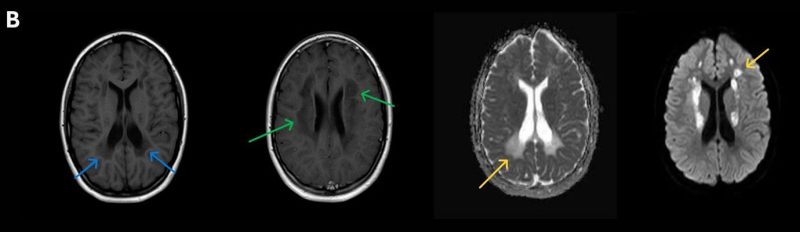

- A) Aksiyel T2A ve koronal T2A sekanslarda sentrum semiovale, korona radiata ve bazal ganglionlar düzeyinde bilateral frontoparietal derin periventriküler beyaz cevherde birleşme eğilimi gösteren hiperintens gliotik sinyal değişiklikleri (oklar) ve aksiyel T2A serilerde servikal spinal kordda posterior kolonda, lateral kesimlerde sinyal artımları (oklar) izlendi.

- B) Kontrastsız T1A serilerde tarifli alanlarda hipointens (oklar) görünüm izlendi. Kontrastlı T1A serilerde bu düzeyde (oklar) kontrastlanma artışı izlenmedi. Diffüzyon ağırlıklı serilerde belirgin diffüzyon kısıtlaması (oklar) görülmedi.

- LBSL, karakteristik radyolojik özelliklere sahiptir. MRG’de tipik olarak bilateral ve simetrik beyaz cevher sinyal değişiklikleri görülürken, subkortikal U lifleri, internal kapsülün posterior kolları, trigeminal sinir traktları, serebellum, korpus kallozumun spleniumu, medulla oblongata ve omurilikteki dorsal kolonlar ile lateral kortikospinal traktlar genellikle korunur.

- Etkilenen bölgelerde T1’de hipointens, T2/FLAIR’da hiperintens sinyal değişiklikleri izlenir. DWI’de lezyonların periferinde kısıtlı difüzyon görülebilir. MRS’de beyaz cevherde laktat artışı saptanabilir, ancak bu her hastada mevcut değildir.

- LBSL tanısında majör kriterler; subkortikal U lifleri korunmuş serebral beyaz cevher, servikal düzey dahil omurilik dorsal kolonları ve lateral kortikospinal traktlar, medulla oblongata piramitleri veya medial lemniskus dekusasyonu tutulumu iken; minör kriterler korpus kallozum spleniumu, internal kapsül posterior kolu, superior ve inferior serebellar pedinküller, trigeminal sinir traktları, mezensefalik trigeminal yollar, medulla oblongata anterior spinosebellar traktları ve serebellar beyaz cevherdeki sinyal değişiklikleridir.